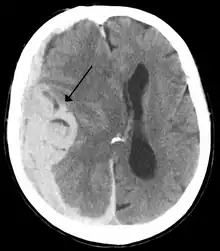

Midline shift is a shift of the brain past its center line.[1] The sign may be evident on neuroimaging such as CT scanning.[1] The sign is considered ominous because it is commonly associated with a distortion of the brain stem that can cause serious dysfunction evidenced by abnormal posturing and failure of the pupils to constrict in response to light.[1] Midline shift is often associated with high intracranial pressure (ICP), which can be deadly.[1] In fact, midline shift is a measure of ICP; presence of the former is an indication of the latter.[2] Presence of midline shift is an indication for neurosurgeons to take measures to monitor and control ICP.[1] Immediate surgery may be indicated when there is a midline shift of over 5 mm.[3][4] The sign can be caused by conditions including traumatic brain injury,[1] stroke, hematoma, or birth deformity that leads to a raised intracranial pressure.

Doctors detect midline shift using a variety of methods. The most prominent measurement is done by a computed tomography (CT) scan and the CT Gold Standard is the standardized operating procedure for detecting MLS.[5] Since the midline shift is often easily visible with a CT scan, the high precision of Magnetic Resonance Imaging (MRI) is not necessary, but can be used with equally adequate results.[5] Newer methods such as bedside sonography can be used with neurocritical patients who cannot undergo some scans due to their dependence on ventilators or other care apparatuses.[6] Sonography has proven satisfactory in the measurement of MLS, but is not expected to replace CT or MRI.[6] Automated measurement algorithms are used for exact recognition and precision in measurements from an initial CT scan.[7] A major benefit to using the automated recognition tools includes being able to measure even the most deformed brains because the method doesn’t depend on normal brain symmetry.[7] Also, it lessens the chance of human error by detecting MLS from an entire image set compared to selecting the single most important slice, which allows the computer to do the work that was once manually done.[7]

Three main structures are commonly investigated when measuring midline shift. The most important of these is the septum pellucidum, which is a thin and linear layer of tissue located between the right and left ventricles.[7] It is easily found on CT or MRI images due to its unique hypodensity.[7] The other two important structures of the midline include the third ventricle and the pineal gland, which are both centrally located and caudal to the septum pellucidum.[6][7] Identifying the location of these structures on a damaged brain compared to an unaffected brain is another way of categorizing the severity of the midline shift. The terms mild, moderate, and severe are associated with the extent of increasing damage.